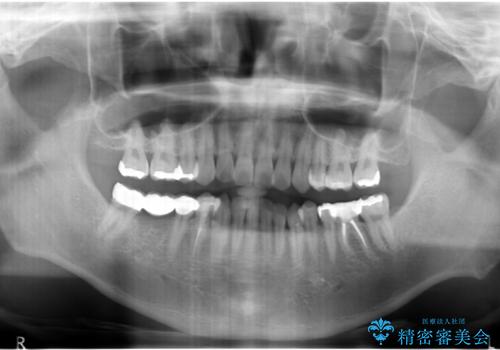

- 全体を見て欲しいと来院。

右下の奥歯の虫歯が大きく、やりかえが難しい状態でした。

外して虫歯を取ったところ。歯茎の深いところまで虫歯があり、やむなく抜歯しました。

右下7については、遠心の歯の高さがなく、また、同様に歯肉縁下にカリエスがあったため、手術を行い改善しました。

右下6については、物理的には歯を使うことは可能ですが、残すと悪くなっていくのを避けられないような修復しかできないため、長期的な展望が立たないため抜歯をお勧めしました。